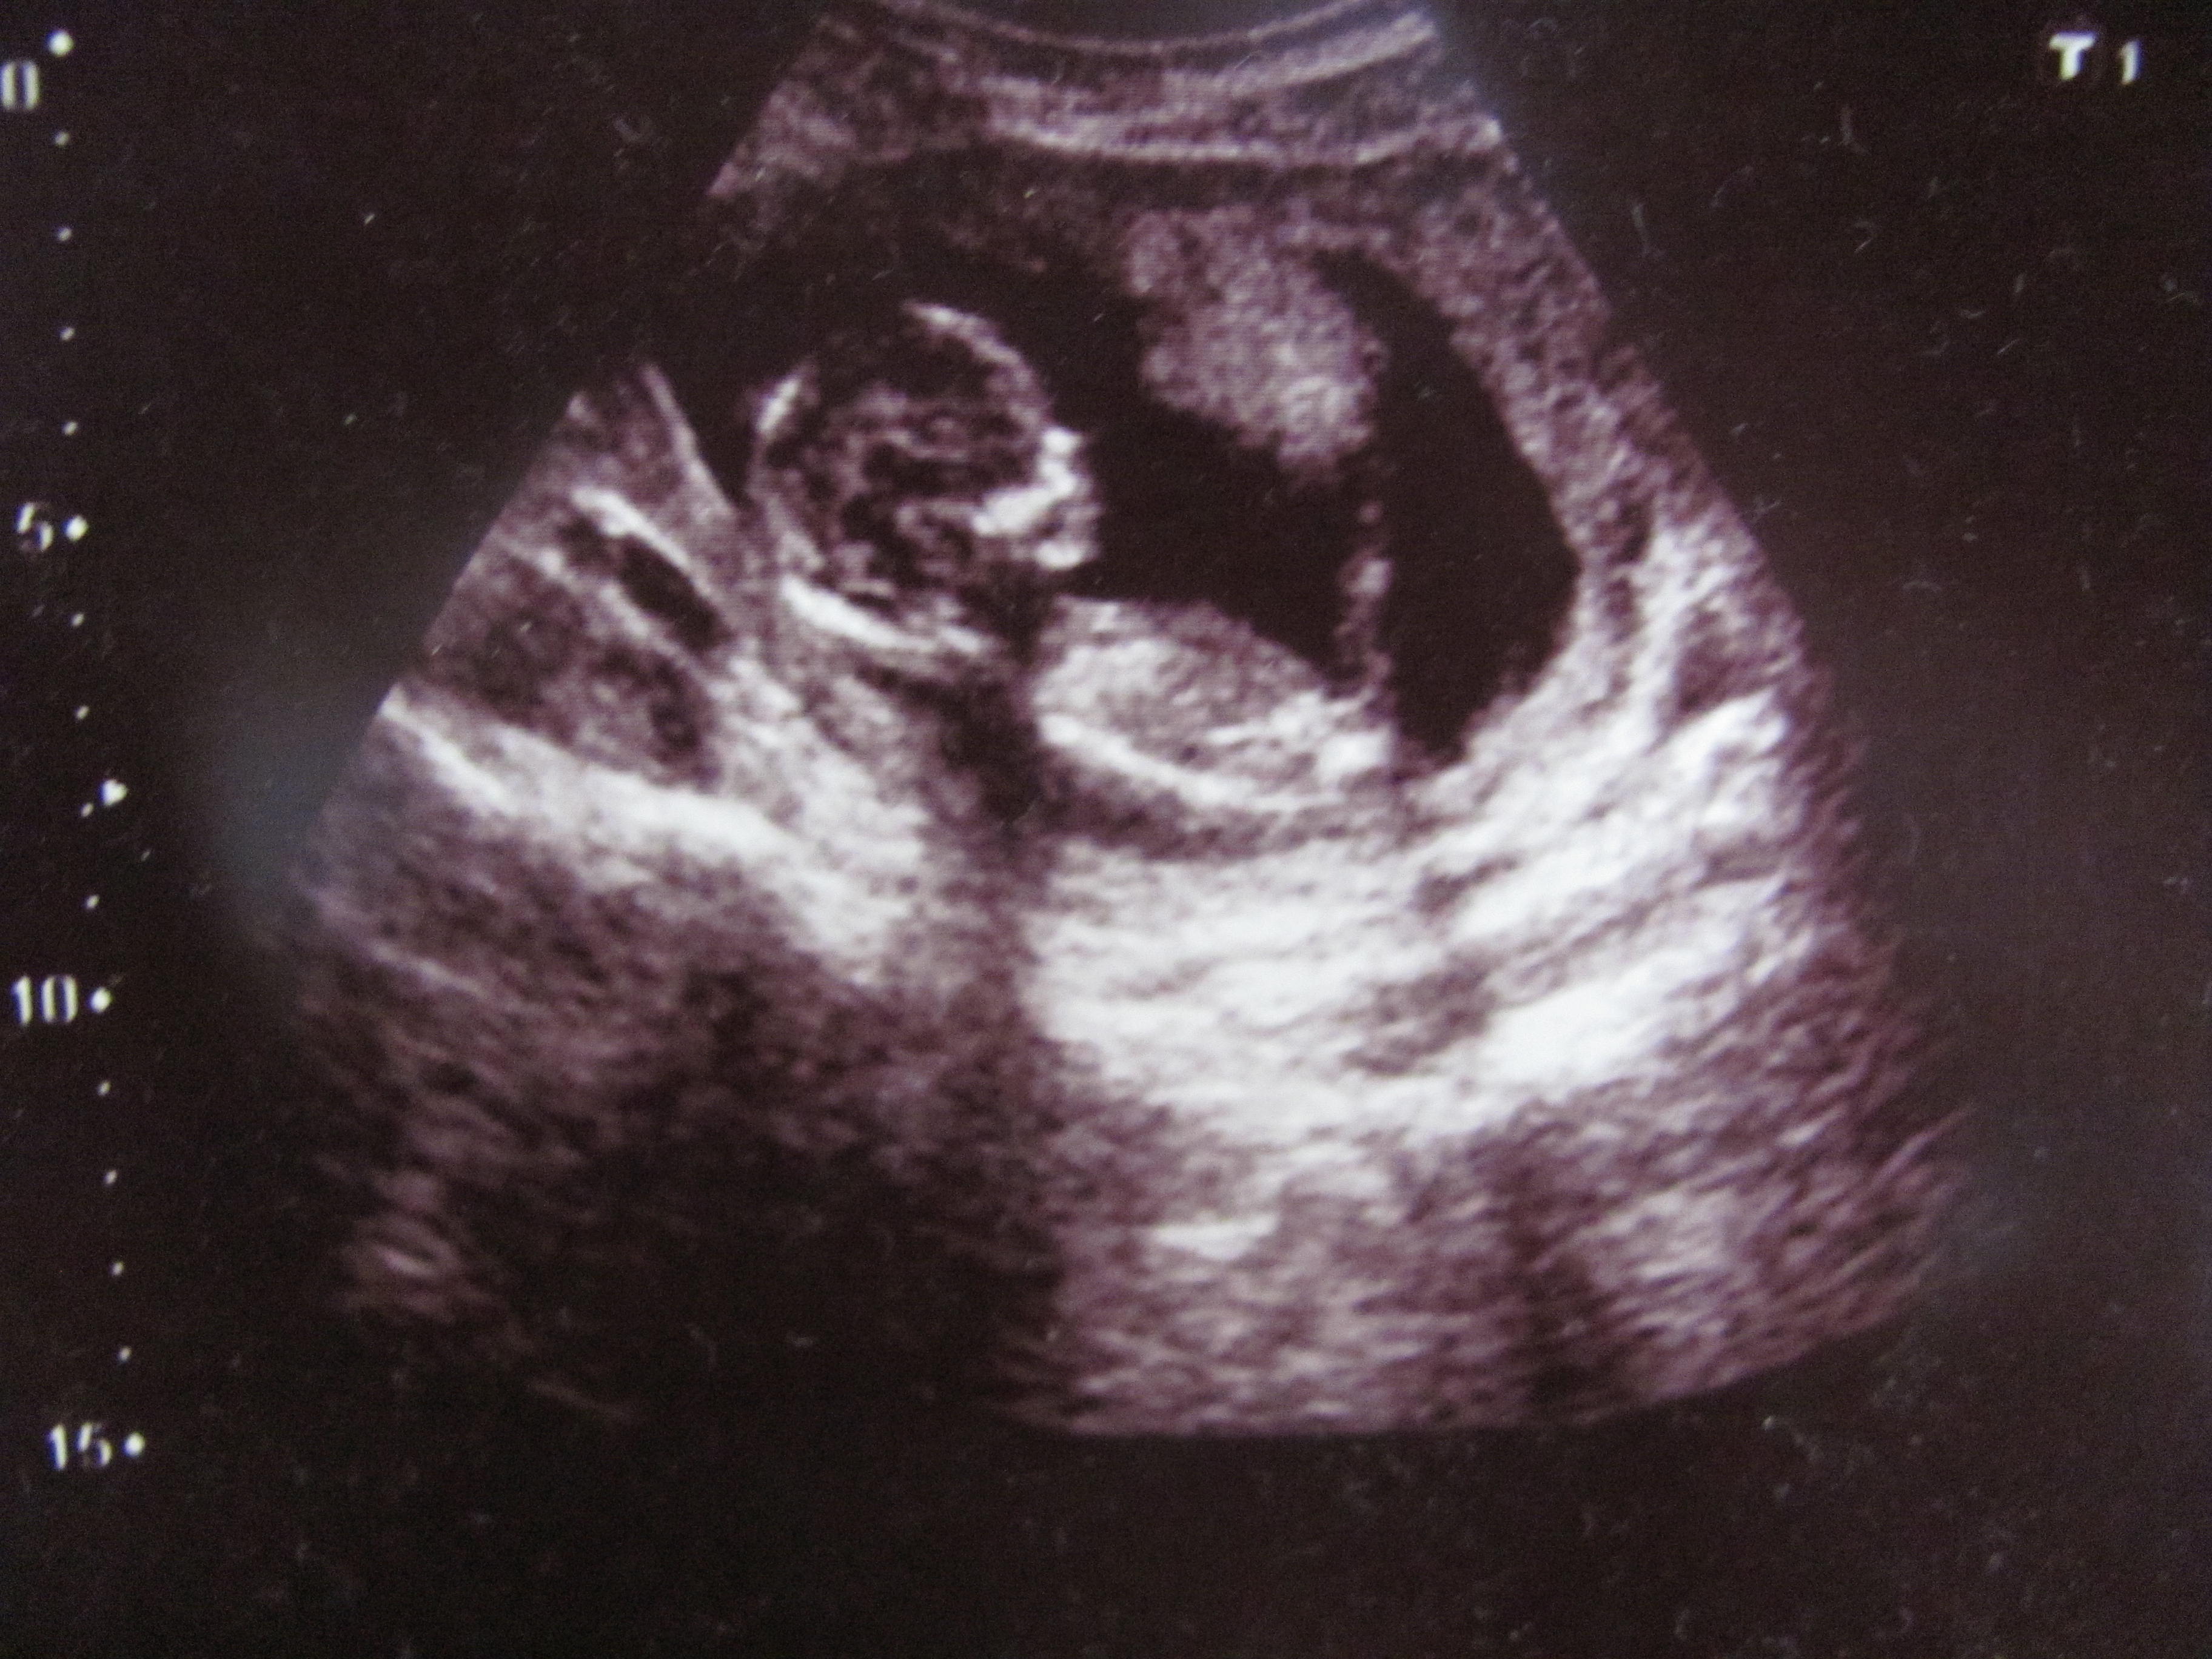

Anyone want to take a guess whether they can see a nub??

Dr confirmed yesterday that we are having a girl indeed. The 3 lines are clearly visible on the scan. :pregnant: